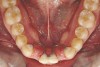

Fig 6 (and Fig 7). Prerestorative orthodontics was completed in 5 months. Final result 3 years, 4 months after completion.

Figure 6

Fig 7 (and Fig 6). Prerestorative orthodontics was completed in 5 months. Final result 3 years, 4 months after completion.

Figure 7